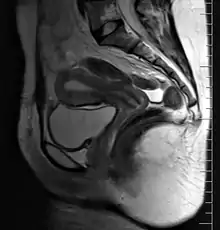

9. Vagina: 10. Hymen; 11. Lumen; 12. Wall; 13. Fornix (lateral)

14. Uterus: Parts: 15. Cervix; 16. Body and 17. Fundus. 18. Orifices: External and Internal; 19. Cervical canal; 20. Uterine cavity; Layers: 21. Endometrium; 22. Myometrium and 23. Perimetrium

24. Fallopian tube: 25. Isthmus; 26. Ampulla; 27. Infundibulum; 28. Fimbria (with 29. Fimbria ovarica)

30. Ovary

31. Visceral pelvic peritoneum: 32. Broad ligament (with 33. Mesosalpinx; 34. Mesovarium and 35. Mesometrium)

Ligaments: 36. Round; 37. Ovarian; 38. Suspensory of ovary

Blood vessels: 39. Ovarian artery and vein; 40. Uterine artery and veins; 41. Vaginal artery and veins

Other: 42. Ureter; 43. Pelvic floor (Levator ani); 44. Femoral head; 45. Hip bone; 46. Internal iliac vessels (anterior branches); 47. External iliac vessels; 48. Abdominal cavity